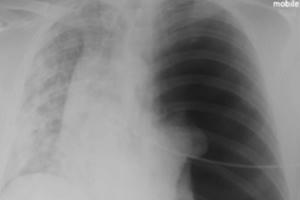

Hình ảnh phổi bị tàn phá của bệnh nhân Covid-19 36 tuổi

Bệnh nhân 36 tuổi đã bị ho khan, sốt và khó thở trong 3 tuần trước khi nhập viện.